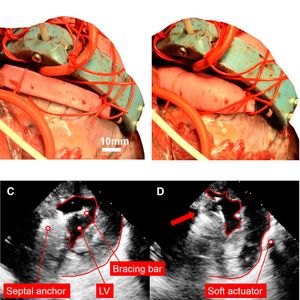

Payne und Kollegen entwickelten deshalb ein Gerät, das durch aufblasbare Kammern von außen Druck auf die erkrankte Herzkammer ausübt, wenn das Blut aus der Kammer ausströmen soll. Wichtig ist ihnen dabei, dass das Gerät über einen Stab in der Herzscheidewand verankert wird. Dadurch wird den Forschern zufolge ein Verzerren der Wand verhindert und sie behält ihre stabilisierende Funktion.

Nachdem die weichen Aktoren auf die Herzkammer gedrückt haben und erschlaffen, ziehen elastische Bänder die Herzkammer wieder in ihre ursprüngliche Form. Hierbei wird Blut in die Kammer gezogen. Sensoren sorgen dafür, dass sich das robotische Gerät der Herzfrequenz des Lebewesens anpasst.

Die sichelförmige Stütze des Geräts ist so gestaltet, dass es sowohl an der linken als auch an der rechten Herzkammer eingesetzt werden kann. Nach verschiedenen Funktionstests setzten die Wissenschaftler das robotische Gerät bei vier Schweineherzen ein. Die Operation kann am schlagenden Herzen durchgeführt werden.